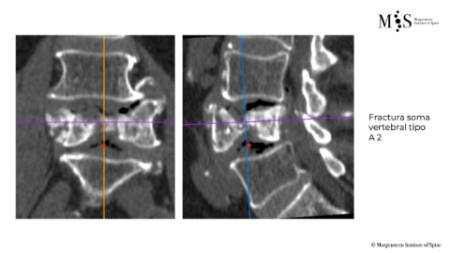

Percutaneous stabilization of unstable vertebral fractures

In cases of complex (unstable, burst, etc.) vertebral fractures, additional stabilization of the fracture by percutaneous stabilization is usually required. In cases where there also is a neurological deficit (muscle weakness, tingling in legs or arms, etc.), a decompression of the spinal canal is additionally required. A percutaneous stabilization of the spine with screws and rods discharges the load on the unstable fracture, stabilizing the whole spine and relieving pain. Depending on the patient’s bone quality, the stabilized vertebrae may be additionally cemented by kyphoplasty.